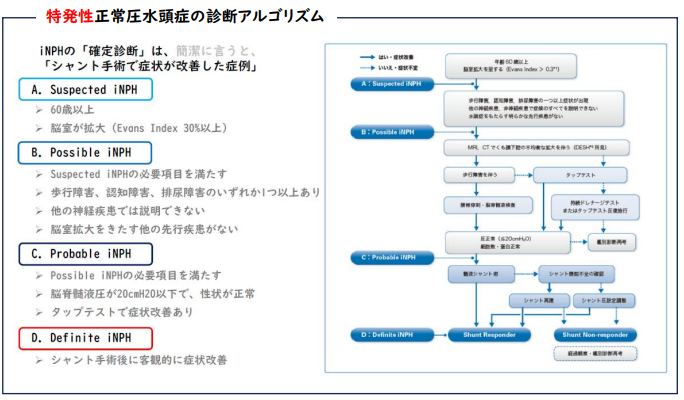

特発性正常圧水頭症の診断は?

特発性正常圧水頭症の診断アルゴリズムを用いて診断していきます。頭部CTやMRIで脳室の拡大がある場合は、特発性正常圧水頭症が疑われます(Suspected iNPH)。

この患者さんが歩行障害、認知機能の低下、排尿障害のいずれかがあり、脳室拡大をきたす他の脳疾患が否定された場合は、特発性水頭症の可能性が高くなります(Possible iNPH)。

このような患者さんにタップテストを行います。タップテストとは、背中から脳脊髄液の一部を抜き取り、症状の改善があるかないかを判断するテストです。局所麻酔で簡単に行うことができます。このテストで症状が改善した場合、特発性正常圧水頭症の可能性がさらに高くなり、患者さんおよびご家族と相談し、シャント手術を受けるか否かを決定します。

不思議に思われるかもしれませんが、実は特発性正常圧水頭症の確定診断は、このシャント手術で症状の改善があったことで初めてなされるのです。